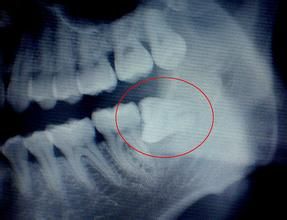

智牙X光攝片臨床表現

6.智齒阻生:通常這是最麻煩的一種。這一種類型的牙齒,通常埋在齒槽骨的裡面,如果經常發生炎症,或是診斷會有病灶發生的時候,就必須拔除了。

智牙 2.造成鄰牙病變:通常患者不自知,而由牙醫以X光診斷得知。通常智齒萌發的空間不足,而會倒在第二大臼齒上,因而造成第二大臼齒清潔不易,甚至是牙齒部分吸收的現象,造成患者不舒適或牙疼。

容納牙齒的頜骨不斷退化變小,因而智齒阻生是必然的結果。拔除阻生的智齒對咀嚼、語言等功能無任何不良影響,加之拔除是治療阻生的最有效的辦法,因此,建議儘早、果斷地拔除引起上述危害的阻生智齒。